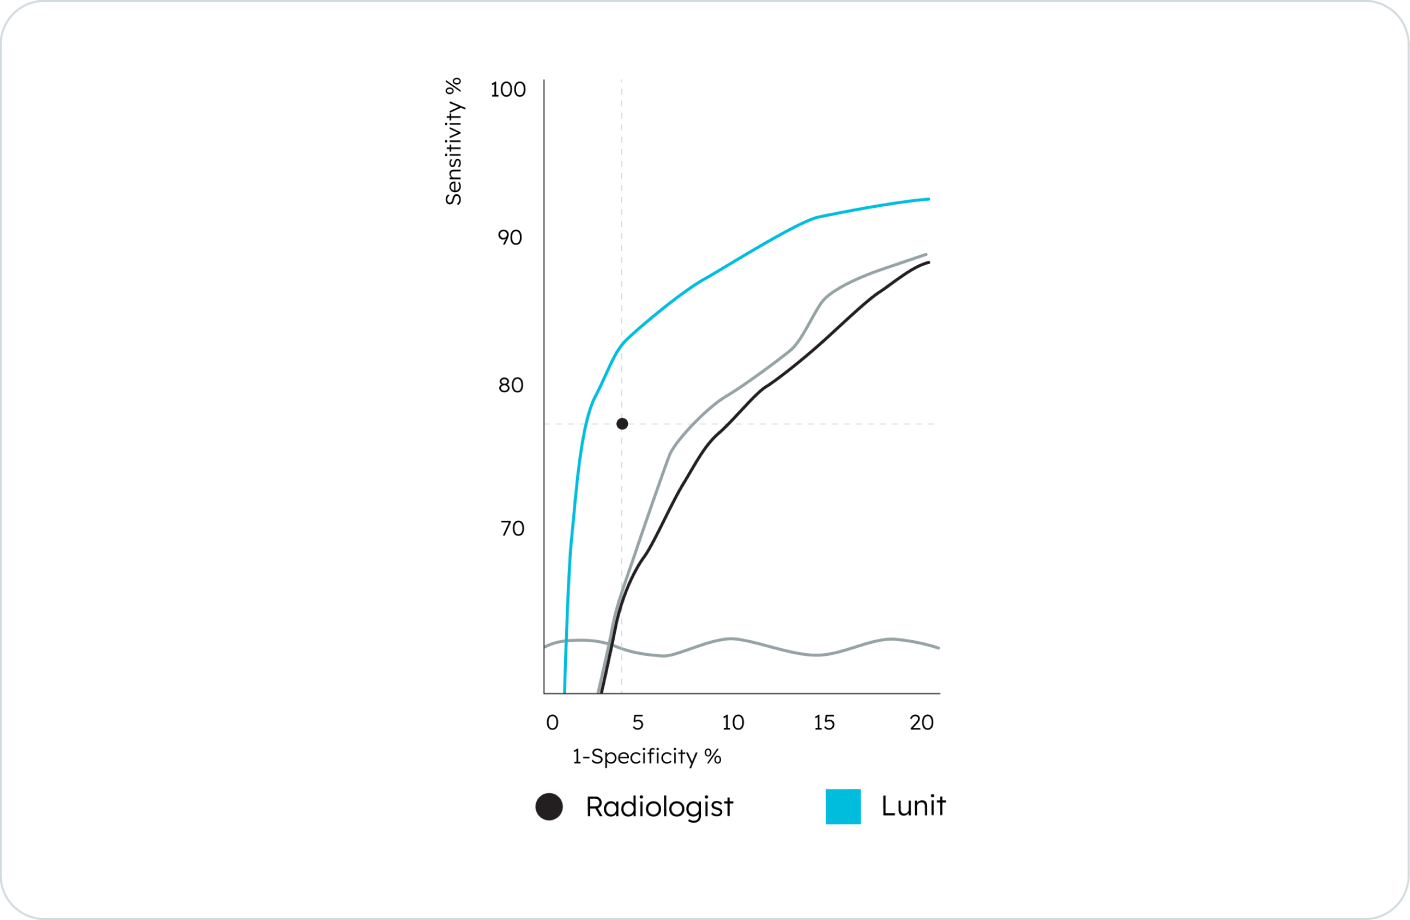

In a JAMA Oncology study, it outperformed other AI solutions with the highest accuracy and optimal sensitivity–specificity in detecting malignant lesions¹.

Lunit INSIGHT MMG has an 18% higher accuracy in extremely dense breasts and an 8% higher accuracy in all breast density categories, enhancing detection across tissue types*.

By improving specificity*, Lunit INSIGHT MMG reduces false positives and unnecessary callbacks. This supports more confident interpretation, lowers patient anxiety, and reduces follow-up burden on clinical teams.